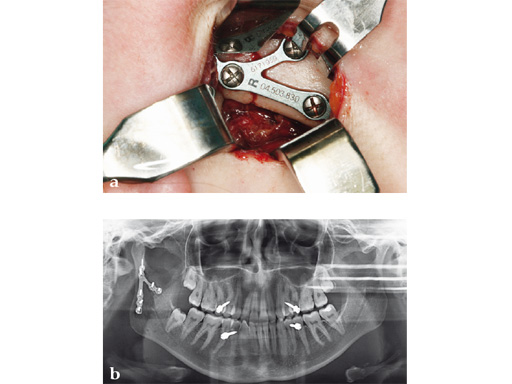

Trapezoidal Plate

The trapezoidal plate is designed to fit the region of the condylar base and provides improved strength and stability over previous single-bar plate designs, thereby eliminating the need to place two plates. It is precontoured to account for the curvature in the transition zone between the base of the condylar process and the adjacent neck. The location of screw holes enables plates to straddle the mandibular foramen and the adjacent canal inlet, thereby avoiding accidental nerve injury. The trapezoidal plate can be applied using external and transoral surgical approaches. If required a transbuccal cannula can be centered in the countersunk screw holes for proper drilling alignment.

Case 3

Case provided by Carl-Peter Cornelius, Mnchen, Germany